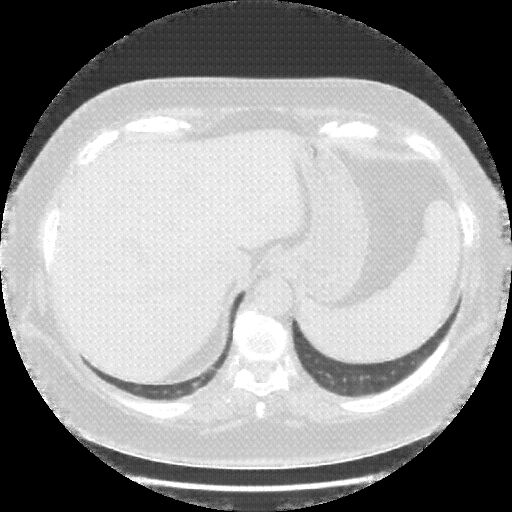

Image Grid

4Γ—3 grid: Rows show different image types (Original NATIVE, Reconstructed NATIVE, Original VENOUS, Generated VENOUS), Columns show windowing techniques (No Window, Lung Window, Mediastinum Window)

Reconstructed NATIVE CT scan (cycle consistency)

No window - Raw intensity values